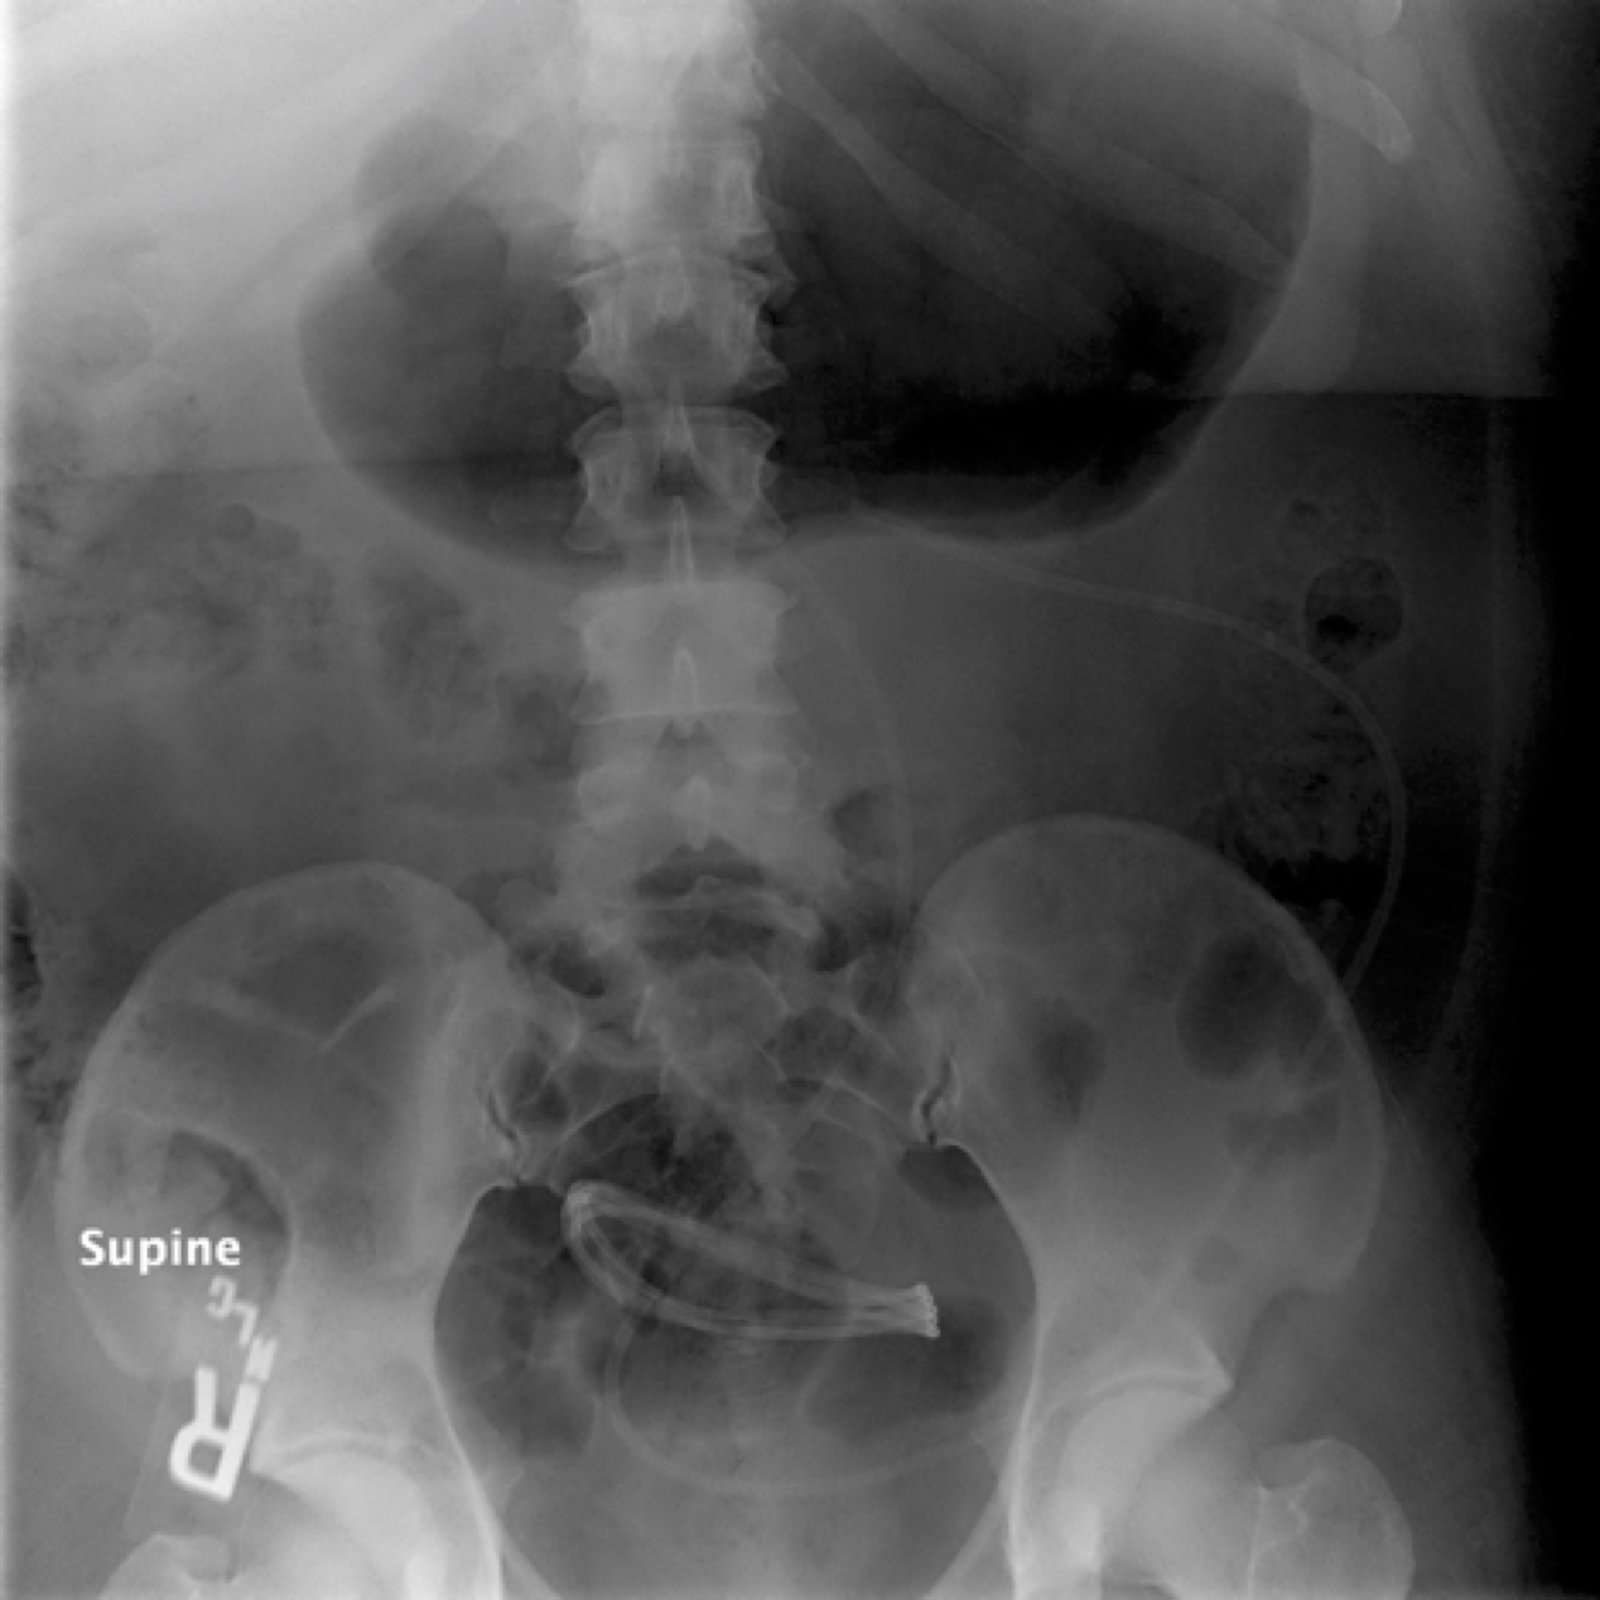

An immediate post-op abdominal x-ray performed after the patient’s VP shunt revision 30 days prior to this ED visit reveals the VP shunt tip in the mid abdomen. A CT of the abdomen performed on the day of the ED visit reveals the VP shunt tip interposed between the spleen and the diaphragm.